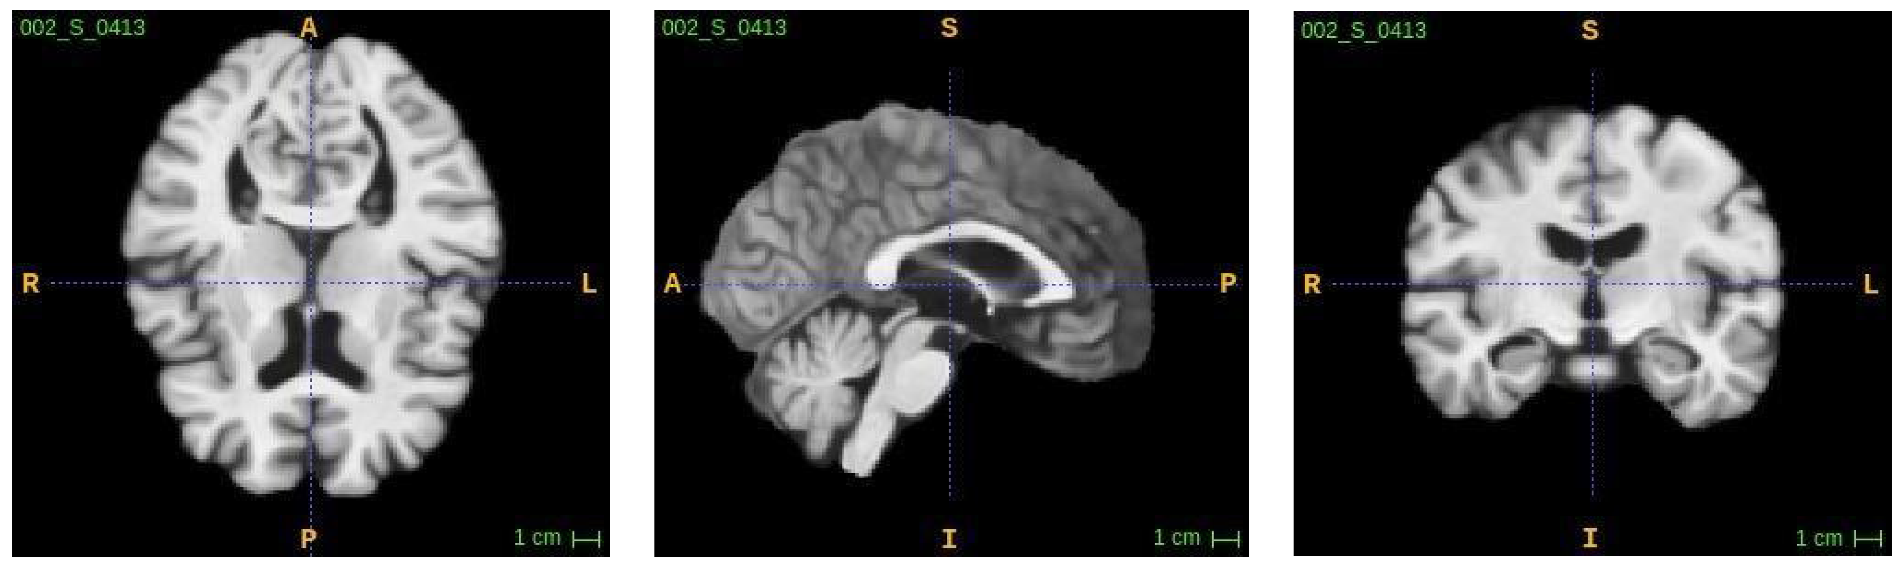

3.1. Multimodal MRI Data Collection

3.2. Image Fusing and Preprocessing